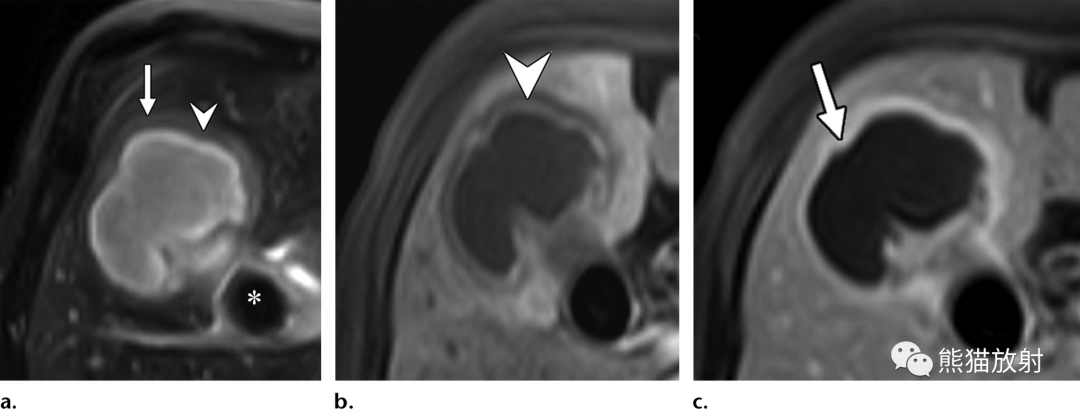

65岁男性,因急性坏疽性胆囊炎发生化脓性肝脓肿。(a)轴位T2WI显示脓肿壁的双靶征,表现为围绕脓肿内部高信号内容物的等低信号内层(箭头)和中等高信号外层(箭)。注意胆囊颈部嵌顿的低信号结石 (*)。(b)轴位对比增强动脉期脂肪抑制T1WI图像显示内层早期强化(箭头)和邻近节段性肝实质充血。(c)轴位对比增强延迟期图像显示内层和外层延迟强化(箭)。